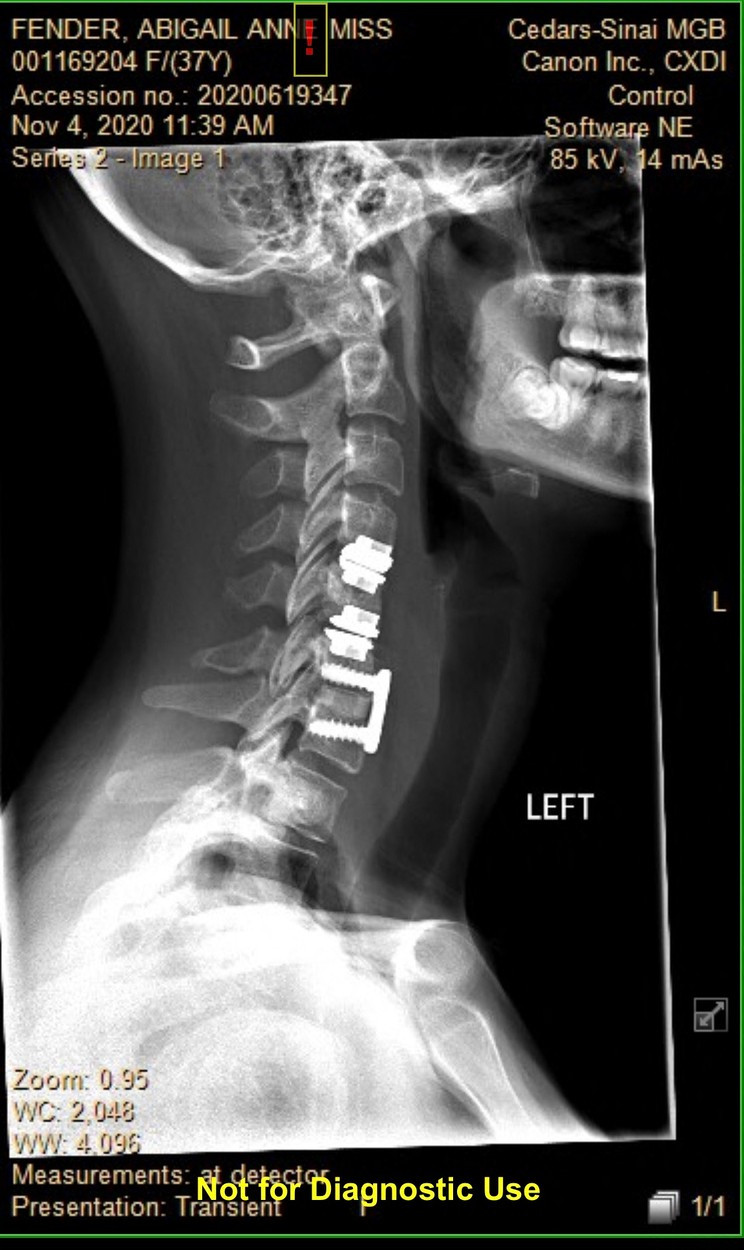

O femeie din Texas a avut parte de un șoc când s-a trezit din anestezie după o intervenție chirurgicală pentru o hernie de disc și a constatat că că vorbește cu accent, și nu reușește să își recapete vocea și tonul ei normale.

Medicii au fost surprinși să constate că femeia suferă de sindromul accentului străin - o afecţiune neurologică rară, care apare în general din cauza traumelor severe aduse creierului, de obicei prin lovire sau accident vascular. Sunt unele cazuri însă, în care nu poate fi stabilită cauza nu poate fi stabilită.